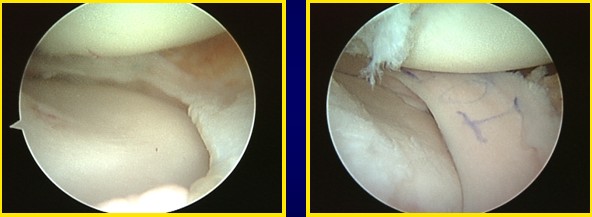

This is an example of a medial meniscus transplant in one of my patient.

This is a video of the patient’s transplanted medial meniscus at 3 months after the surgery.